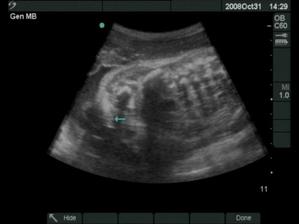

18.12.2008 prišli na svet o 3 týždne skôr naše krásne dvojičky. Ako prvá predrala cestu svojmu bratčekovi Laura, ktorá išla hlavičkou. Prišla na svet 12:53 a vážila 2720 g a merala 46 cm. Marko mal výjsť hneď na to zadočkom, ale keď zistil že sa mu uvoľnilo miesto asi si to rozmyslel a rozhodol sa v brušku zostať a spriečil sa. Pán doktor ho musel síce trochu povykrúcať aby ho dostal von, ale našťastie sa mu to podarilo a nemuseli maminu po normálnom pôrode aj rezať 🙂 Svetlo sveta uzrel Marko 13:03 a vážil 2890 g a meral 48 cm.